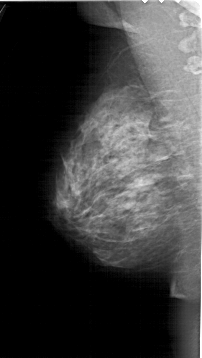

A_1664_1.RIGHT_MLO

RIGHT_MLO LINES 6226 PIXELS_PER_LINE 3346 BITS_PER_PIXEL 12 RESOLUTION 43.5 OVERLAY